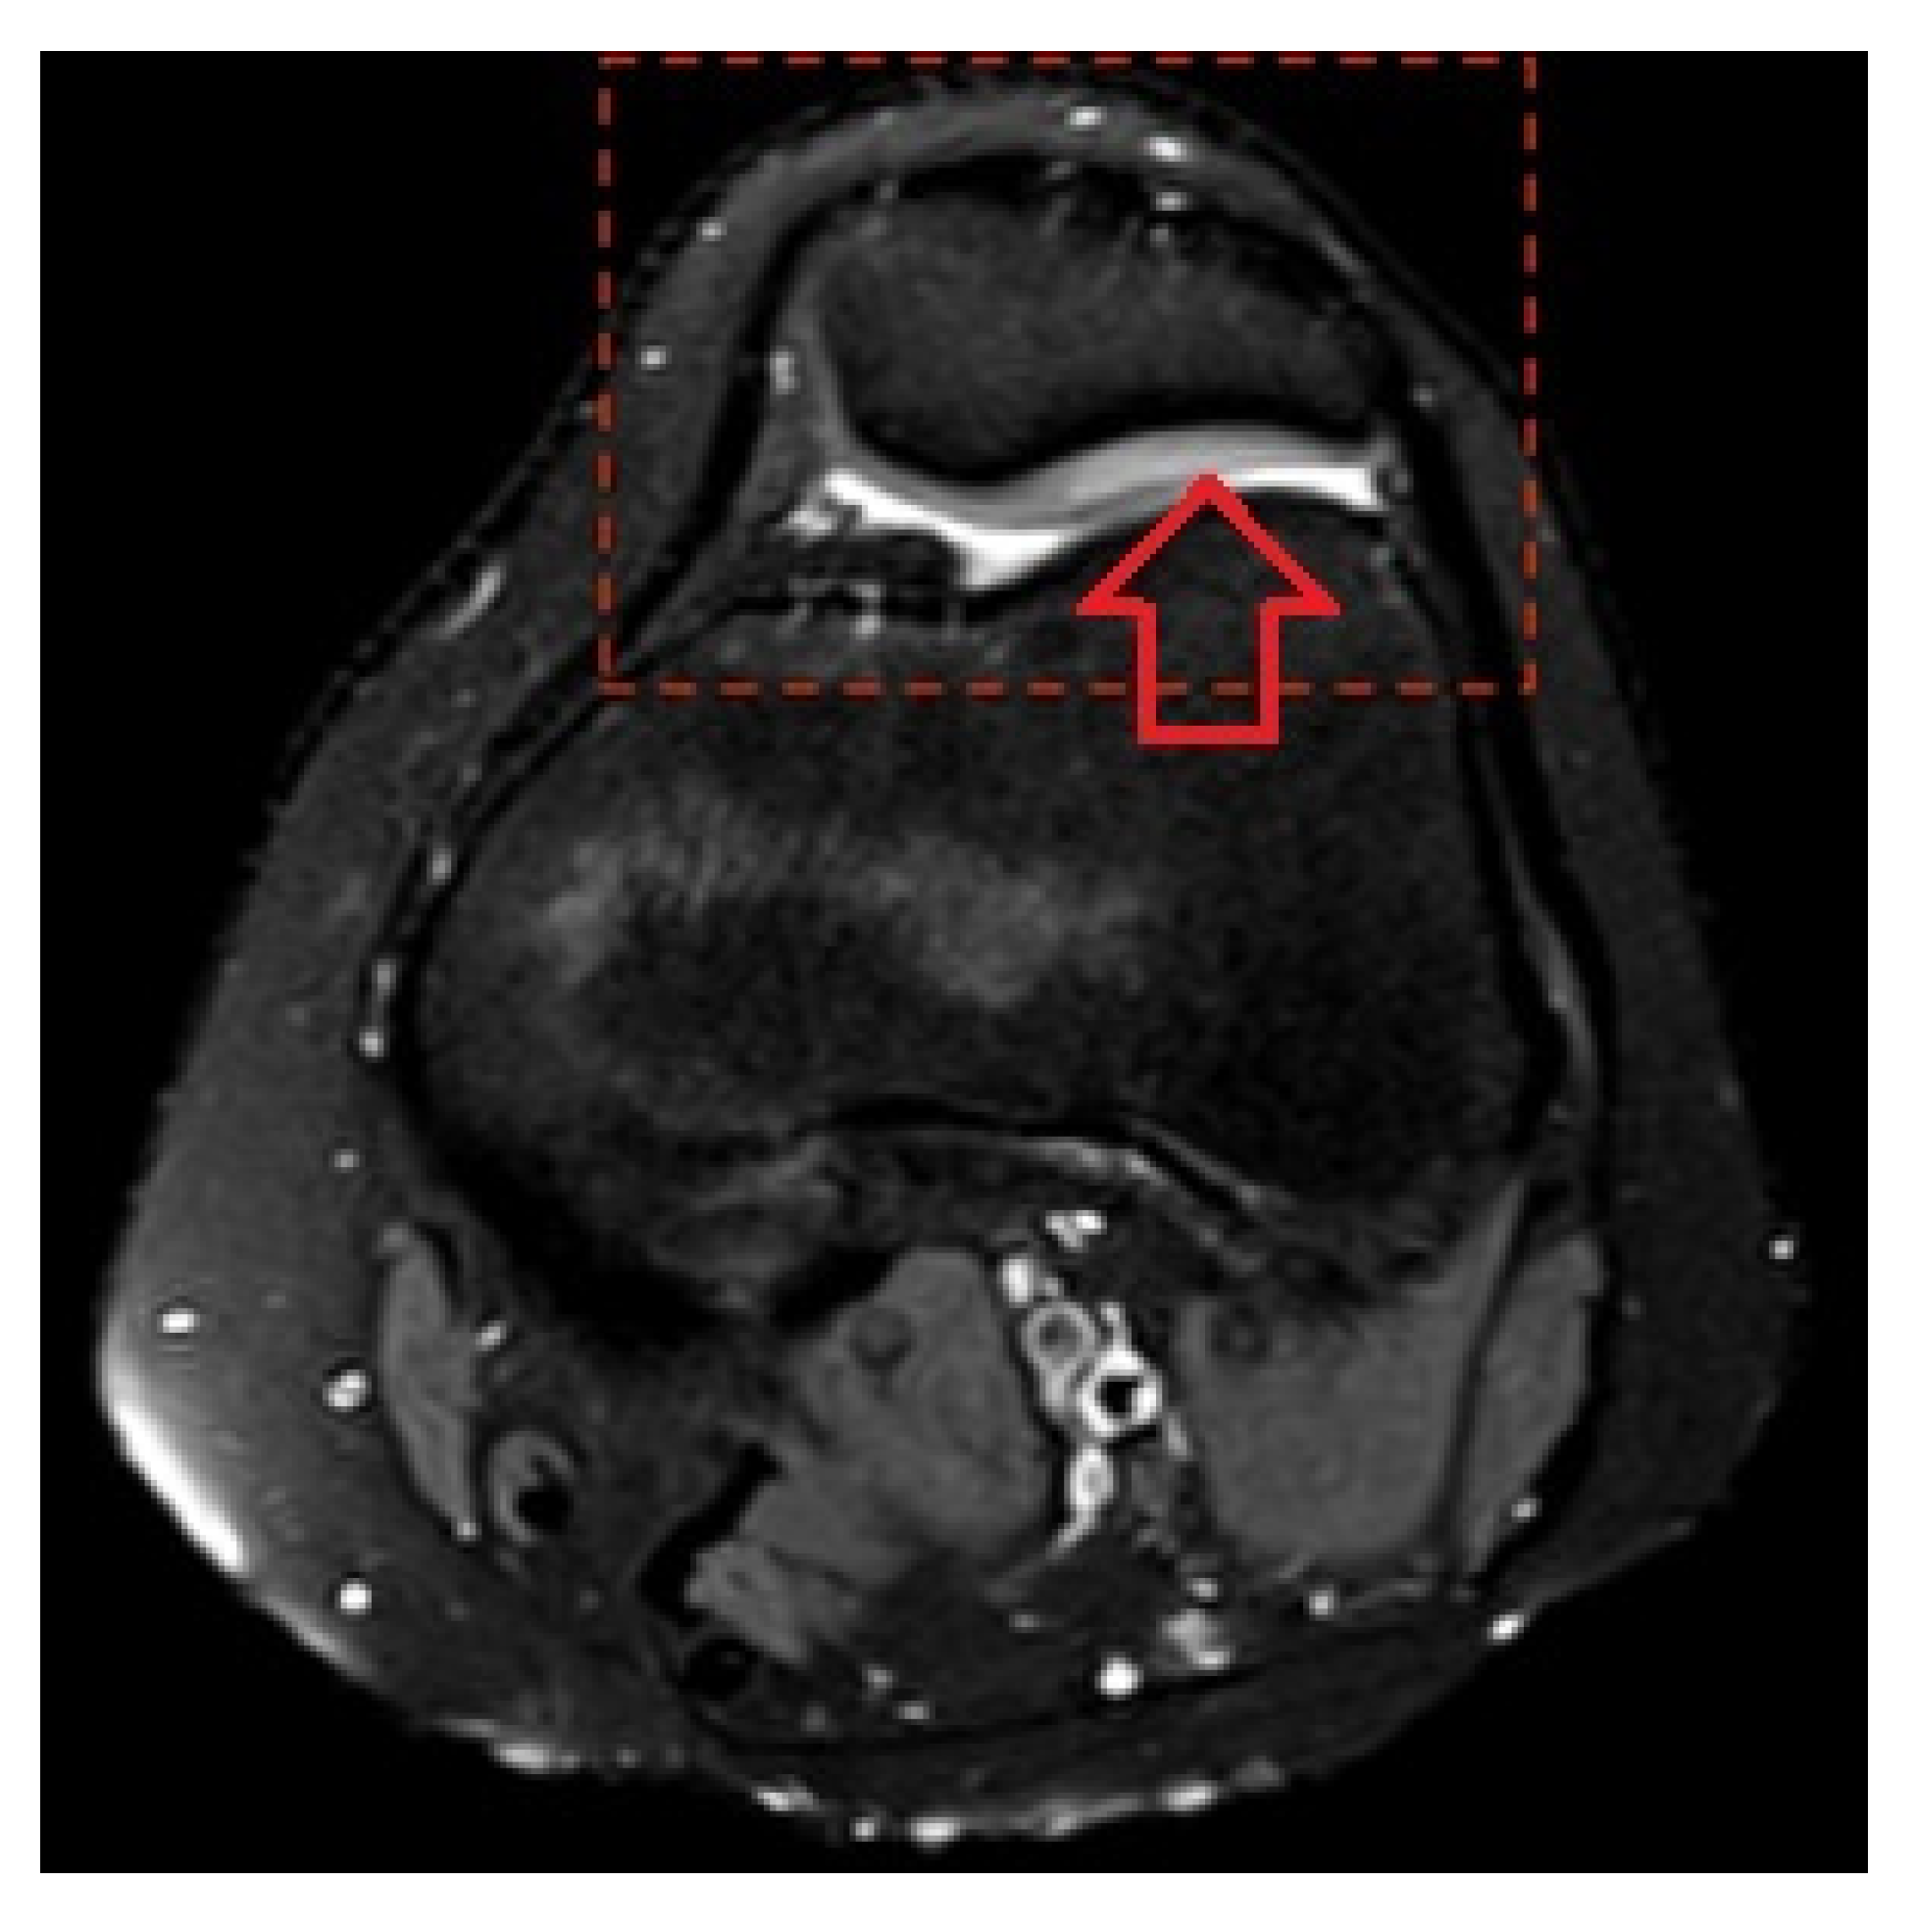

The Magnetic Resonance Imaging Pattern of the Lesions Caused by Knee Overuse in the Pediatric Population